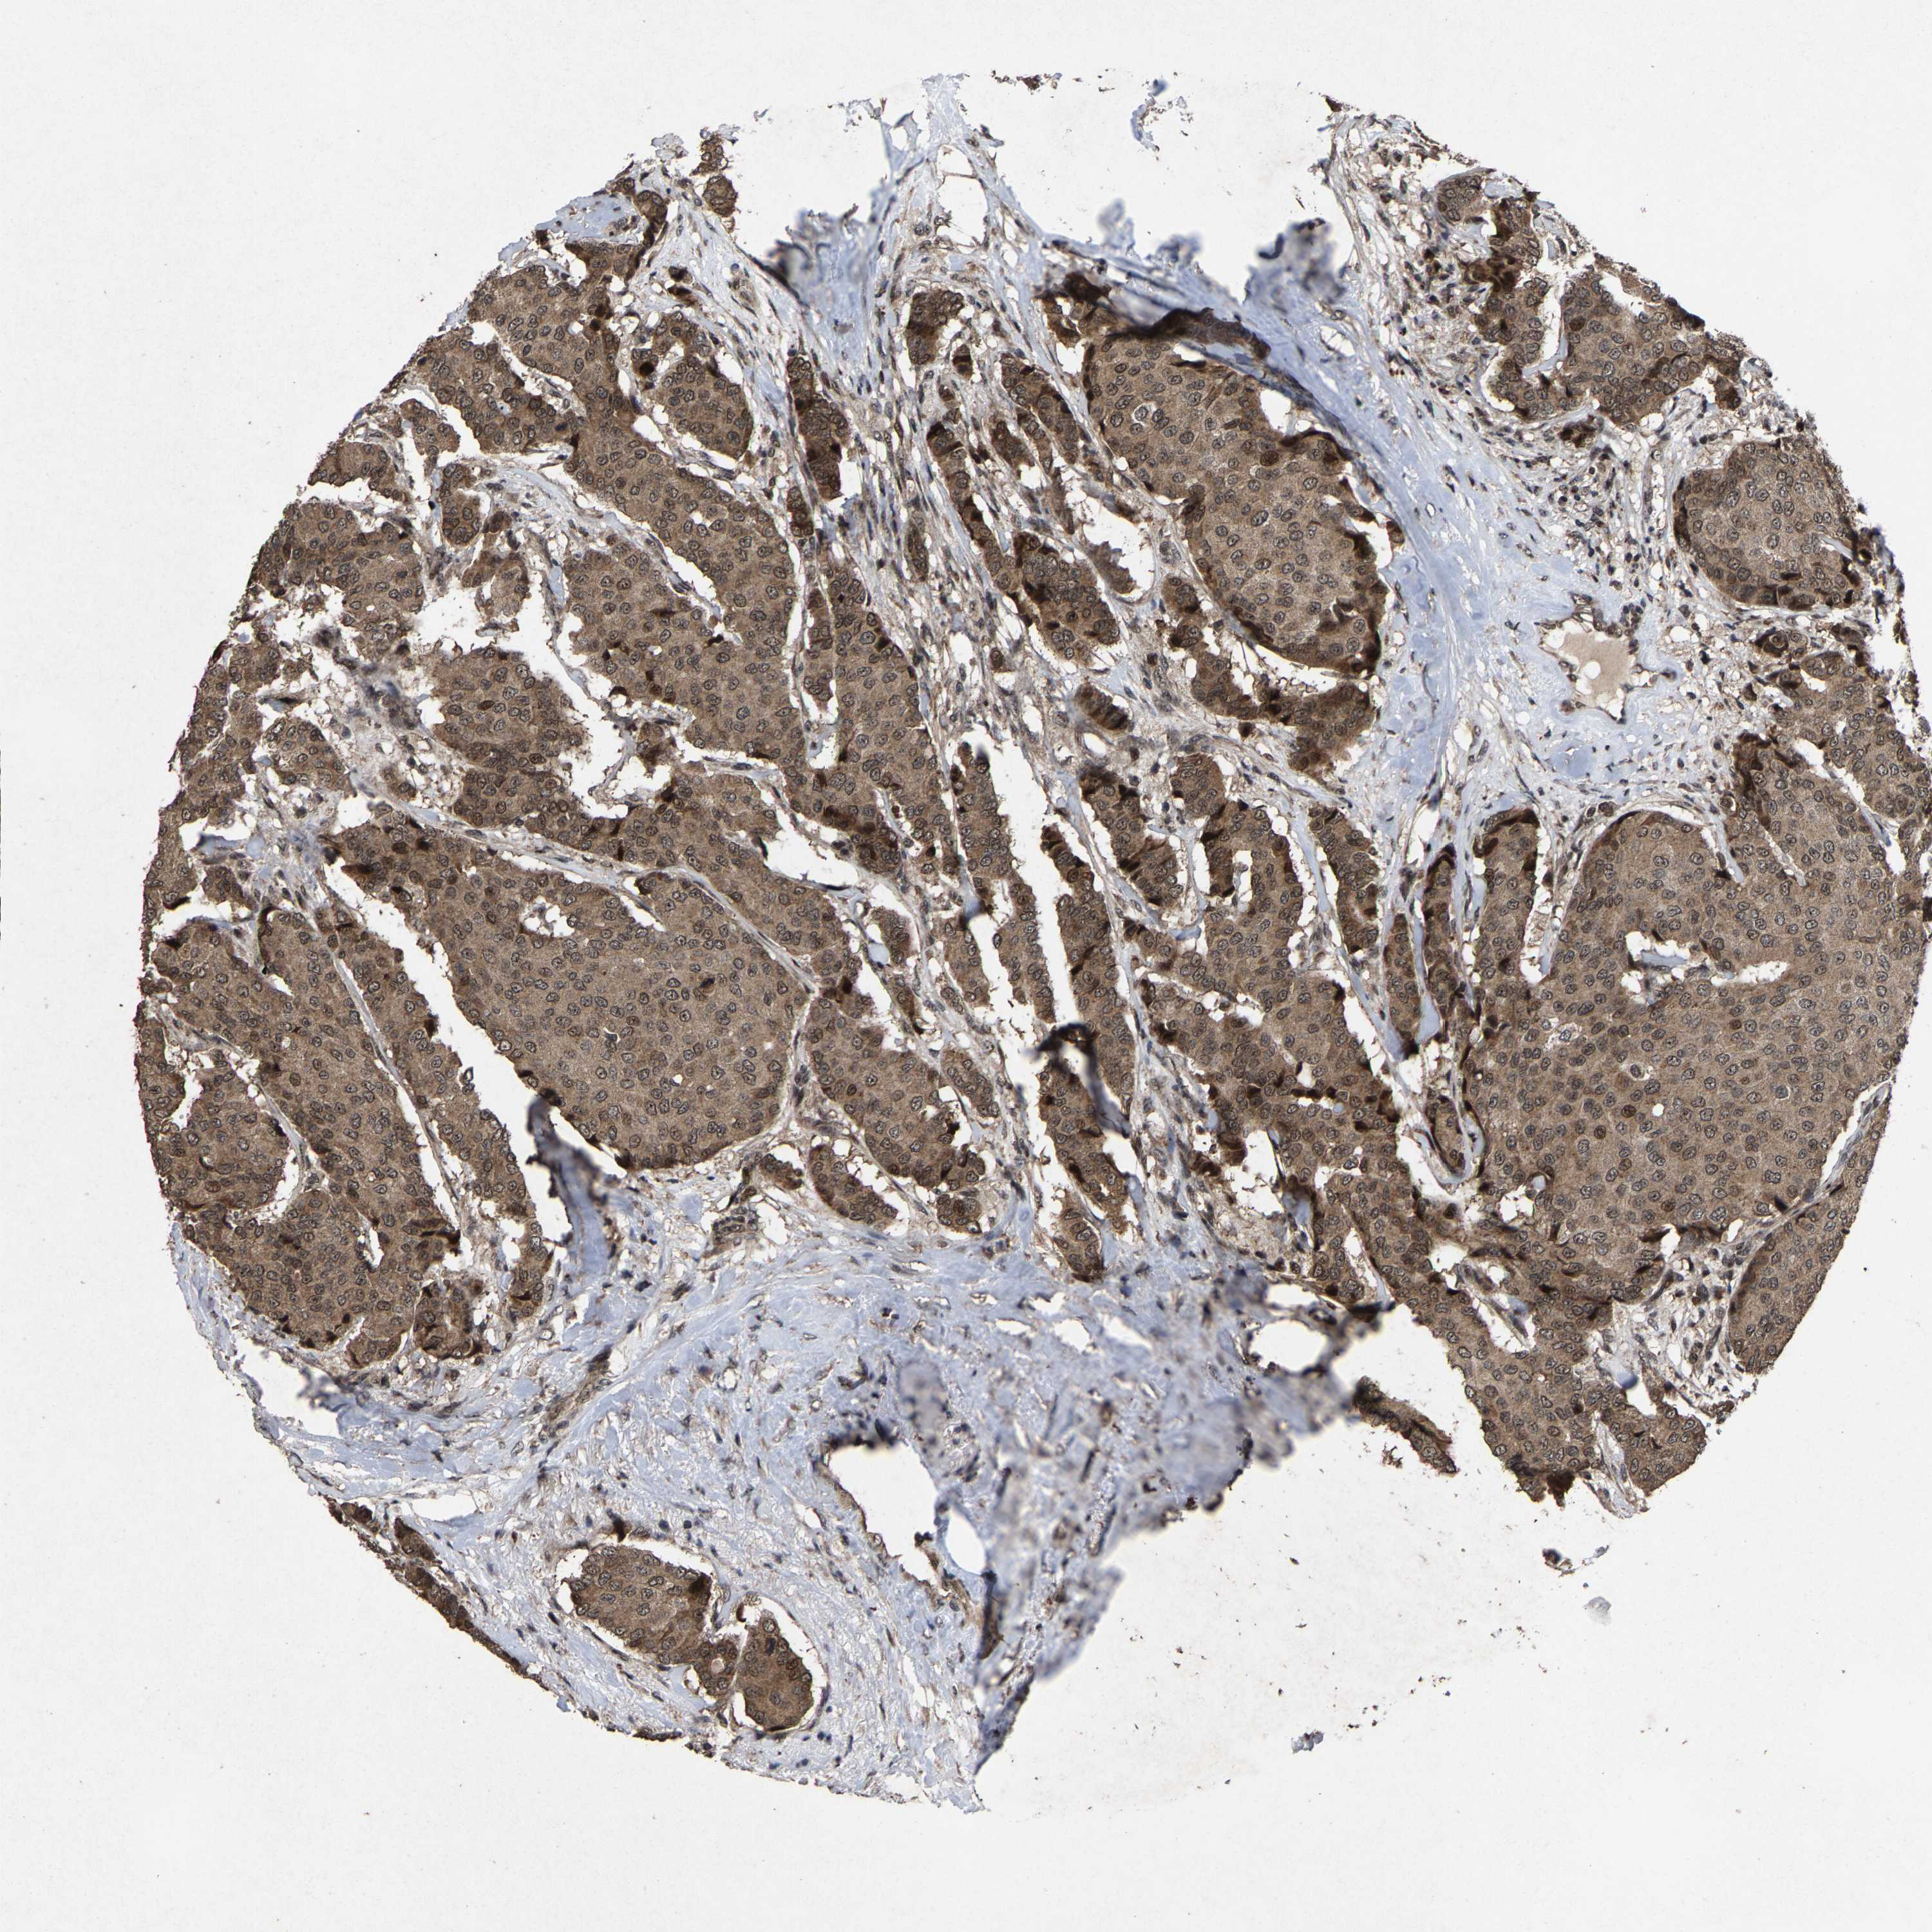

BRCA TCGA BRCA VALIDATION PROTEIN EXPRESSION